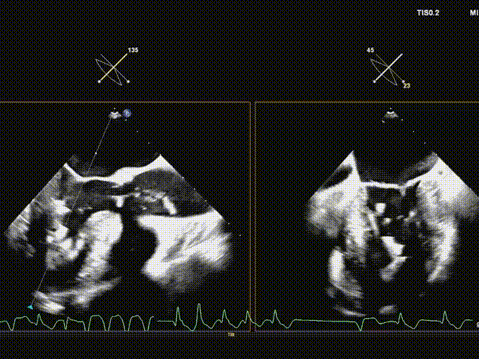

超声引导导丝跨瓣成功;

确认导丝在心尖部;

22mm球囊预扩;

输送系统顺利过弓及跨瓣;

快速起搏下初次释放瓣膜,瓣膜开口形态不好,位置偏高;

遂回收瓣膜,重新跨瓣并调整瓣膜释放位置后;

快速起搏下再次释放瓣膜至工作位,超声评估开口形态可,位置深度满意;